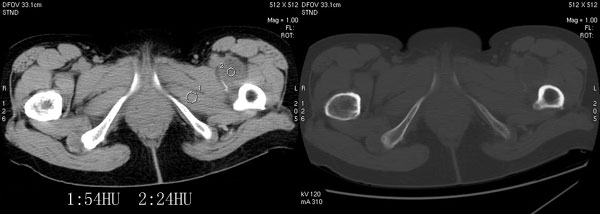

以下是引用jiajie在2006-7-14 17:19:00的发言:[br]ct所见:双侧髋关节不对称,左侧关节间隙变窄,关节面毛糙。左侧股骨头变形、无明显变小,前上缘与髋臼融合,融合处骨质明显增生硬化,并见数个小囊变影。股骨头下端与股骨颈交界部见囊样变,邻近肌肉内见囊样密度减低区,ct值24hu。右侧髋关节形态未见异常。[br][br]ct诊断:左侧髋关节结核可能,请结合临床资料进一步分析。

以下是引用lihuuuu在2006-12-5 10:14:00的发言:[br]定位像示:左侧髋臼变浅,倾斜度加大,髋臼外上缘呈波浪状不规则,骨质增生硬化,髋关节上缘间隙明显变窄,股骨头向外上轻度移位。轴位像示:左侧股骨头变形,前上缘与髋臼融合,融合处骨质明显增生硬化,并见数个小囊变影。股骨头下端与股骨颈交界部见囊样变,邻近肌肉内见密度减低区,ct值24hu,内缘见弧形高密度钙化影。右侧髋关节形态未见异常。[br]ct诊断:左侧髋臼发育不良[br] 左侧股骨头缺血性坏死[br] 左侧肌肉内低密度影伴有高密度钙化-考虑早期骨化性肌炎[br] [br]“我认为在描述上已经写了肌肉部分,印象诊断里应该写主见”[br]